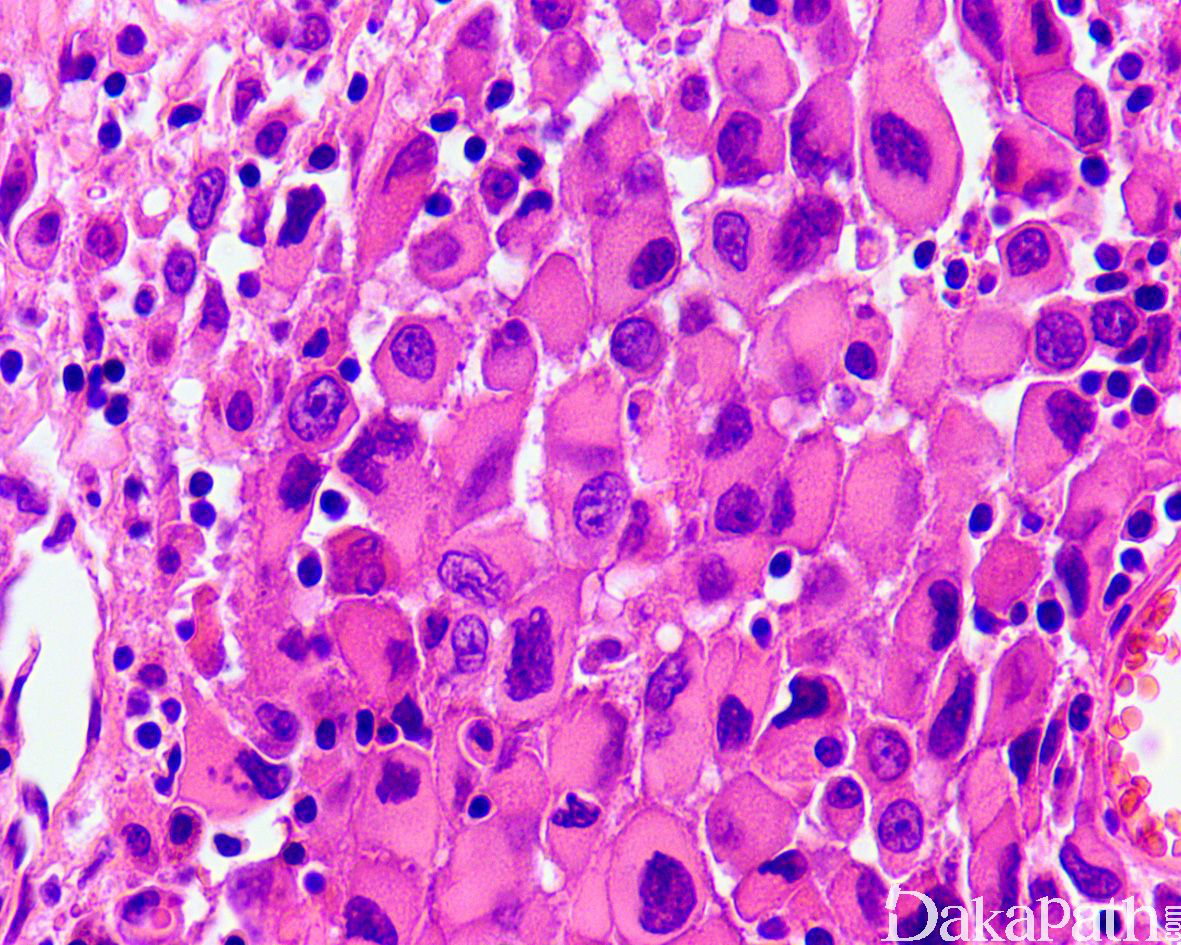

近端型:

呈多结节性,以上皮样细胞为主,梭形细胞少;

上皮样细胞大而圆,有明显的异型性,染色质呈空泡状,可见明显的核仁,常见坏死;

部分区域可见横纹肌样瘤细胞,当横纹肌样瘤细胞较多时,可称为具有横纹肌样上皮样肉瘤。